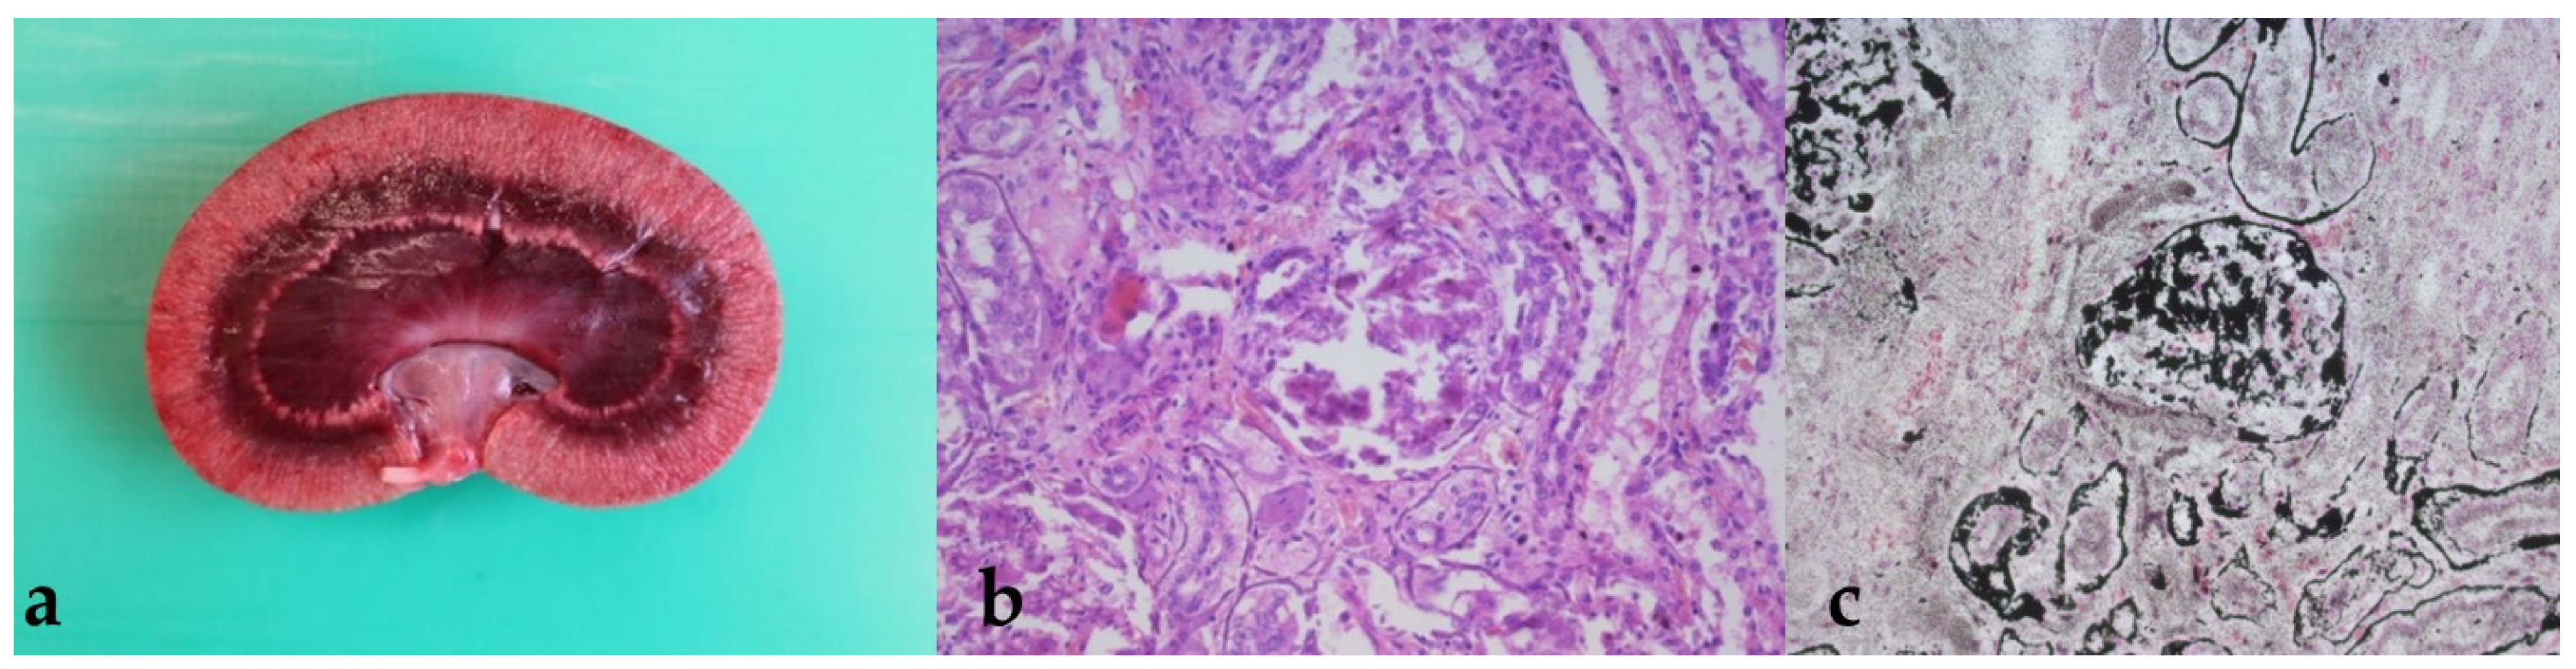

3.4. Findings from the Pathological Examination